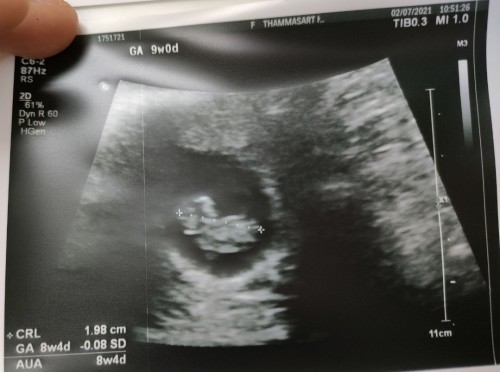

ตอน 9 วีคค่ะ ตอนนี้ 12วีคแล้ว